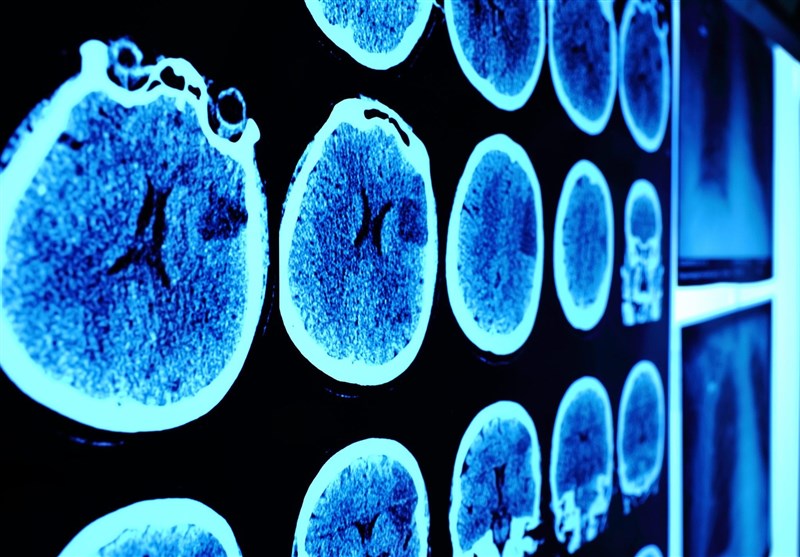

کاهش حجم ماده خاکستری مغز در بیماران حاد ویروس کرونا

طبق تحقیقات جدید دانشمندان افرادی که به بیماری کرونا مبتلا شده و دچار کمبود اکسیژن و تب می‌‌شوند, با کاهش حجم ماده خاکستری در مغز خود مواجه می‌‌شوند.

اجتماعی

به گزارش خبرنگار اجتماعی باشگاه خبرنگاران پویا؛ بر اساس مطالعه جدیدی که محققان "دانشگاه ایالتی جورجیا" و "انستیتوی فناوری جورجیا" انجام داده‌اند، بیماران کووید19 که تحت درمان با اکسیژن درمانی هستند و  یا دچار تب می‌‌شوند, با کاهش حجم ماده خاکستری در شبکه پیشانی مغز مواجه می‌شوند.

پایگاه خبری "نیوز مدیکال" در این باره نوشت, این مطالعه نشان داد حجم ماده خاکستری کمتری در این ناحیه مغزی حتی با گذشت 6 ماه از ترخیص از بیمارستان با سطح بالاتری از ناتوانی در بیماران کرونایی همراه است.

ماده خاکستری برای پردازش اطلاعات در مغز حیاتی است و این کاهش ممکن است بر عملکرد و ارتباط نورون‌ها در مغز تاثیر بگذارد؛ این مطالعه که در مجله "Neurobiology of Stress" در ماه مه 2021 منتشر شده است، نشان می‌دهد ماده خاکستری در شبکه پیشانی می‌تواند یک منطقه اصلی برای درگیری مغز در بیماران کووید19 باشد؛ حتی فراتر از آسیب‌های جدی مانند سکته مغزی.

محققان در تصویربرداری عصبی و اسکن توموگرافی کامپیوتری در 120 بیمار از جمله 58 بیمار مبتلا به کووید19 حاد و 62 بیمار بدون ویروس کرونا با سن و جنس متفاوت دریافتند که ماده خاکستری در مبتلایان به ویروس کرونا بیشتر تحت تاثیر قرار می‌گیرد.

تجزیه و تحلیل‌ها نشان داد که بیماران دارای سطح بیماری بالاتر در هنگام ترخیص و 6 ماه بعد حتی هنگام کنترل بیماری‌های عروقی مغزی، حجم ماده خاکستری کمتری در شبکه پیشانی مغز دارند.

حجم ماده خاکستری در این منطقه در بیماران دریافت کننده اکسیژن درمانی در مقایسه با بیمارانی که اکسیژن درمانی دریافت نمی‌کنند نیز به میزان قابل توجهی کمتر است؛ همچنین بیماران دارای تب در مقایسه با بیماران بدون تب نیز با این کاهش قابل توجه در حجم ماده خاکستری روبه‌رو هستند.

یافته‌ها حاکی از آن است که ماده خاکستری موجود در شبکه قدامی می‌تواند نشانه نقش منطقه اصلی مغز در کووید19 باشد.